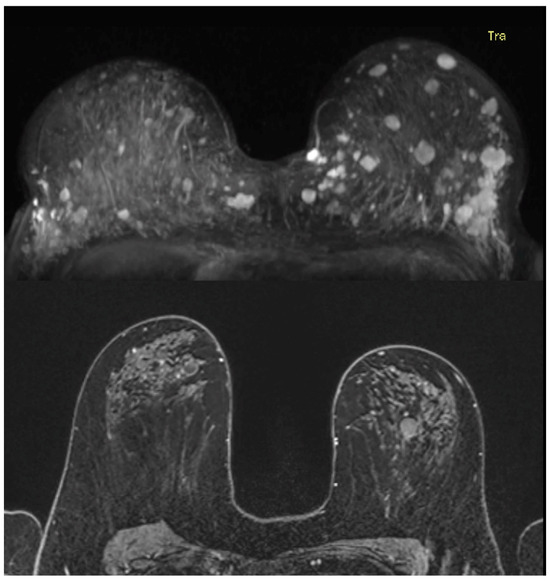

3.2. Magnetic Resonance Imaging Features and Corresponding Pathology Outcome of Breast Cancers